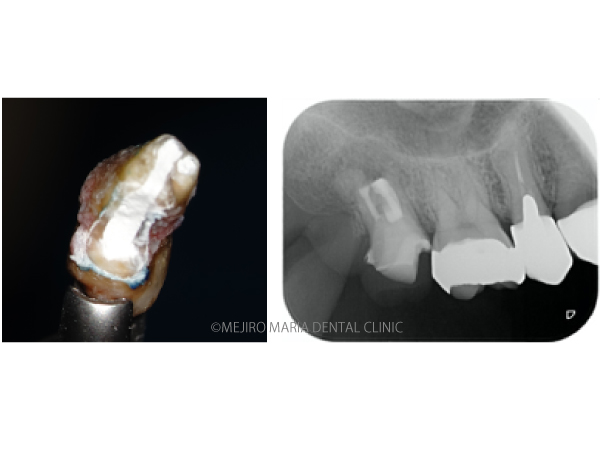

歯牙を抜歯後、メチレンブルーにて染色して破折線を確認しました。破折線に沿って感染部位を除去しましたが、根管内部の構造が非常に複雑なため、最終的な形態は、真ん中の写真のようにしました。

治療のコンセプト通り、根管内部を超音波と歯科用タービンを使用して根尖方向から洗浄しました。その後はMTAにて歯内を封鎖し、抜歯窩へ歯牙を戻して手術は終了しました。